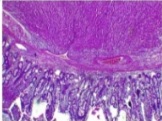

Tháo lồng thấy đầu lồng là một khối u ruột non kích thước khoảng 3cm nghi ngờ u gist, mạc treo ruột tương ứng không thấy hạch (Hình 3 và 4). Tiến hành cắt đoạn hỗng tràng kèm u với sinh thiết lạnh diện cắt âm tính. Phục hồi lưu thông tiêu hóa bằng nối hỗng- hỗng tràng tận tận. Quá trình hậu phẫu thuận lợi, không xảy ra biến chứng gì, bệnh nhân xuất viện sau 7 ngày. Kết quả giải phẫu bệnh lý sau mổ: mô bệnh học phù hợp với u gist đường tiêu hóa typ tế bào hình thoi ở ruột non, nguy cơ cao(Hình. 5). Bệnh nhân được tái khám khoa ung bướu sau 1 tháng.

Hình 5. Hình ảnh vi thể